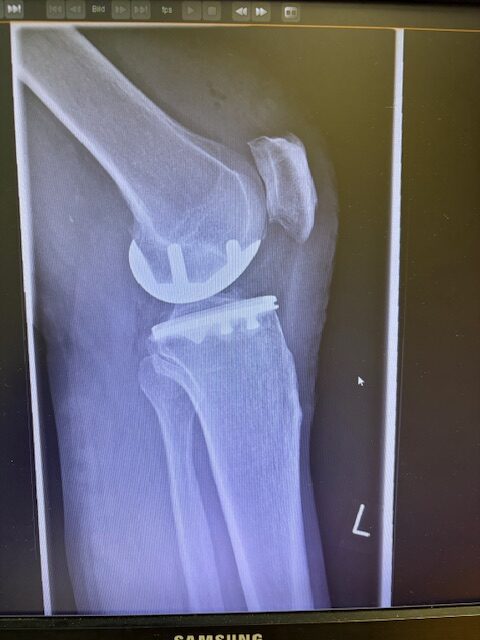

Η επέμβαση πραγματοποιήθηκε με ελάχιστα επεμβατική προσπέλαση και τοποθέτηση πρόθεσης μόνο στον έσω μηροκνημιαίο διαμέρισμα του γόνατος.

Η ακριβής προσαρμογή του εμφυτεύματος επιβεβαιώθηκε διεγχειρητικά, εξασφαλίζοντας σταθερότητα και φυσική κίνηση της άρθρωσης.

Στον ασθενή τα εμφυτεύματα που χρησιμοποιήθηκαν είναι της εταιρείας Zimmer-Biomet Persona Μηριαίο μέγεθος 6, κνημιαίο μέγεθος Η και ενθέμα (inlay) Η li. 8mm.